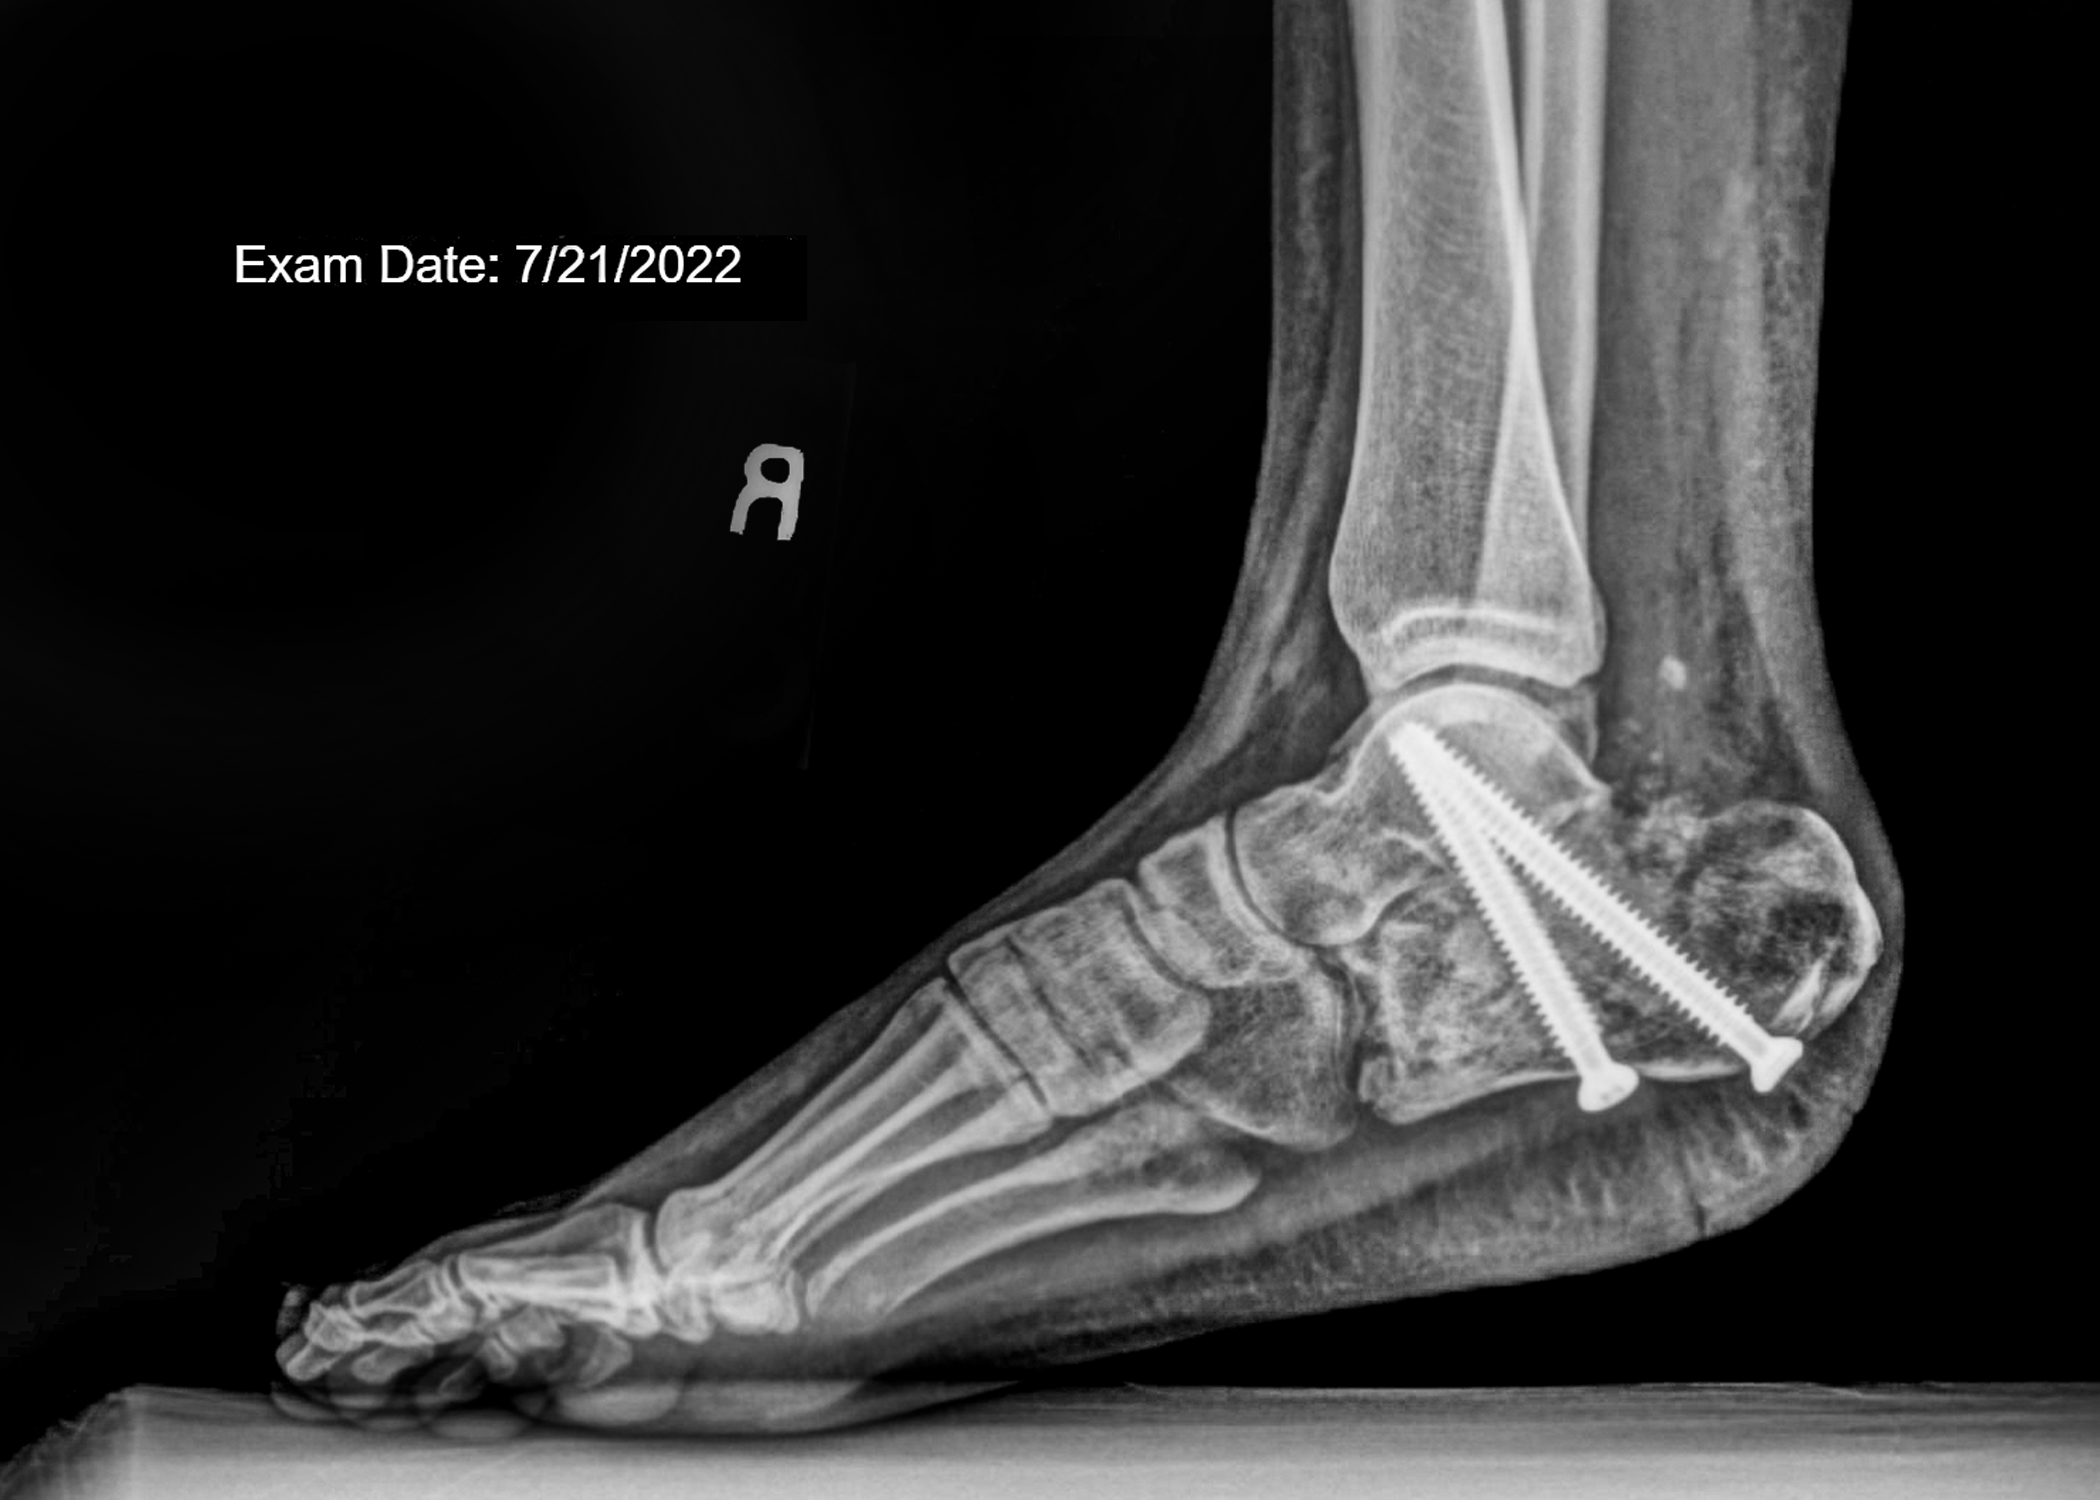

faux flowers X-rays, and tape installation

“Those sounded like terrible memories to have. I wonder if they will ever come back. I hope they don’t” -6/14/2022. Although my memories from the fall never came to me, the aftermath can never be forgotten. More than anything, I wanted to find meaning in my accident.